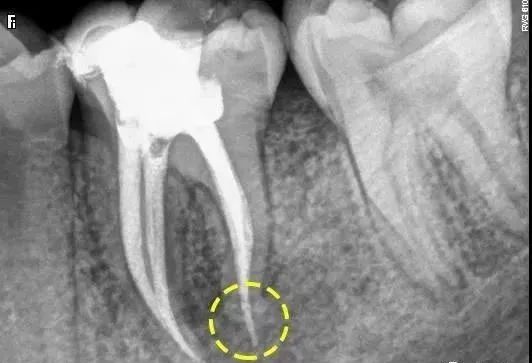

超填通常是由于器械超预备破坏了根尖狭窄区或者预备的根管锥度不佳。由于牙齿自然的根尖吸收或根管清理成形过程中破坏了根尖狭窄而造成根尖孔敞开,加压充填时没有根充挡,压力没有良好控制导致充填材料的超充(如图)。其他原因包括炎症造成的牙根吸收和牙根未发育完善。